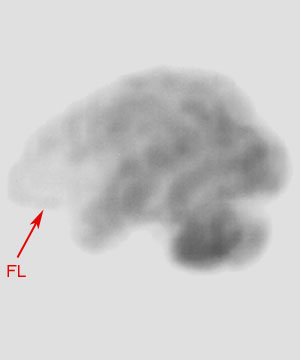

On nuclear SPECT cerebral perfusion images, one may see hypoperfusion defects in the ventromedial frontal region in the frontal variant of Frontotemporal dementia. In the temporal lobe variant of Frontotemporal dementia, SPECT demonstrates hypoperfusion in one or both temporal lobes and anterolateral temporal lobe atrophy involving the polar region, fusiform, inferolateral gyri with sparing of the hippocampal formation may be manifested. Invariably the left temporal lobe is more affected than the right temporal lobe. |

![]() ![]() Both images above are SPECT images using Tc-99 in an individual with Pick's disease. |